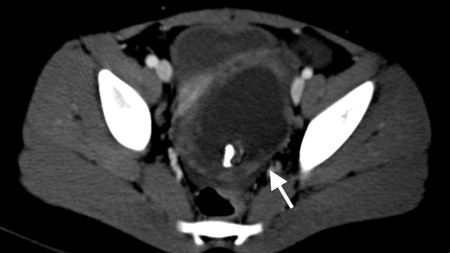

Tomografia computadorizada (TC) revelando fecalito (seta branca) fora do lúmen do apêndice consistente com apêndice perfurado

Do acervo de Dr. KuoJen Tsao; usado com permissão